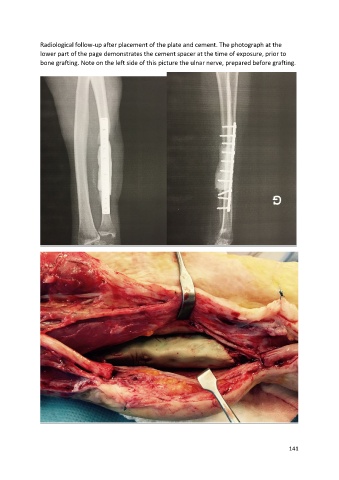

Radiological follow-up after placement of the plate and cement. The photograph at the

lower part of the page demonstrates the cement spacer at the time of exposure, prior to

bone grafting. Note on the left side of this picture the ulnar nerve, prepared before grafting.